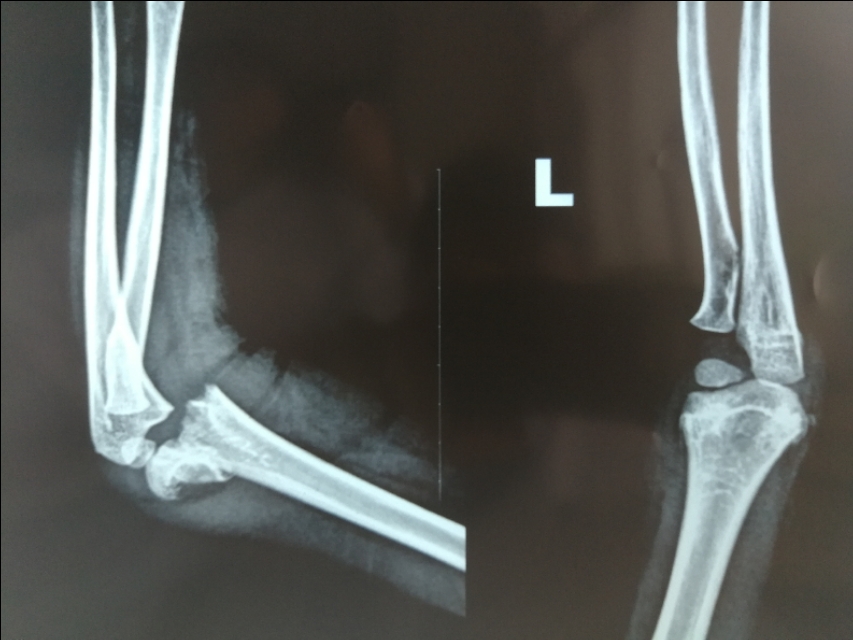

例二:闭合复位,经皮穿针固定